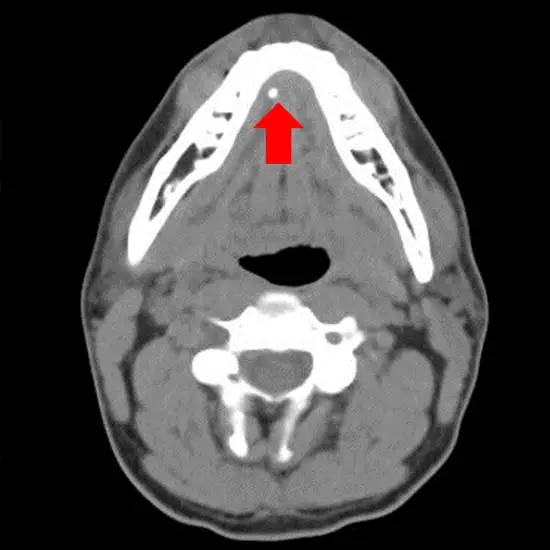

To determine the size of your tumour, your doctor may recommend imaging tests of your parotid gland. If your parotid tumour is cancerous, you may need to have tests to see if the cancer has spread.